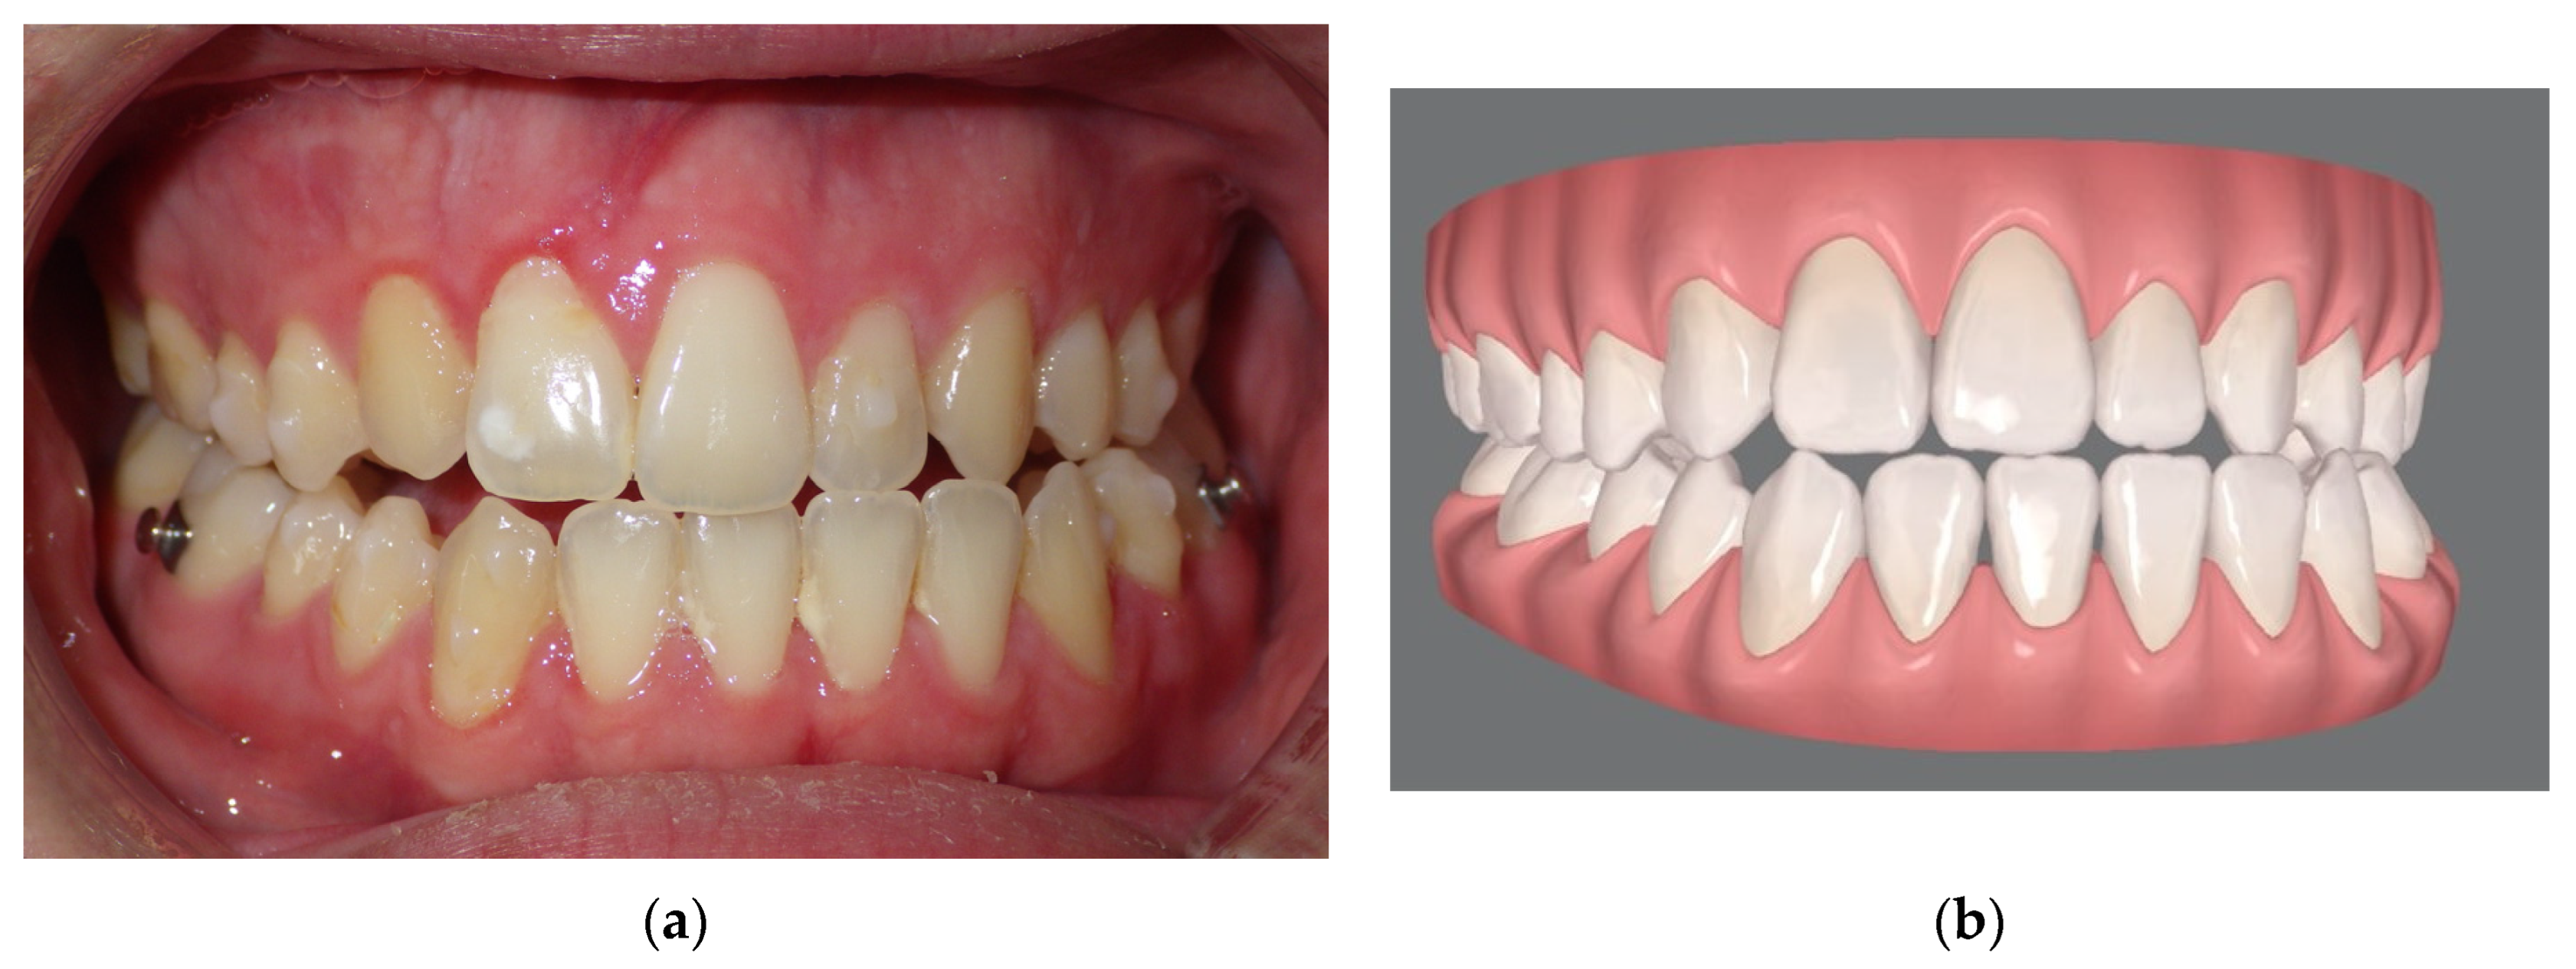

Pre-Surgical Orthodontic Treatment

- Clear aligner technique